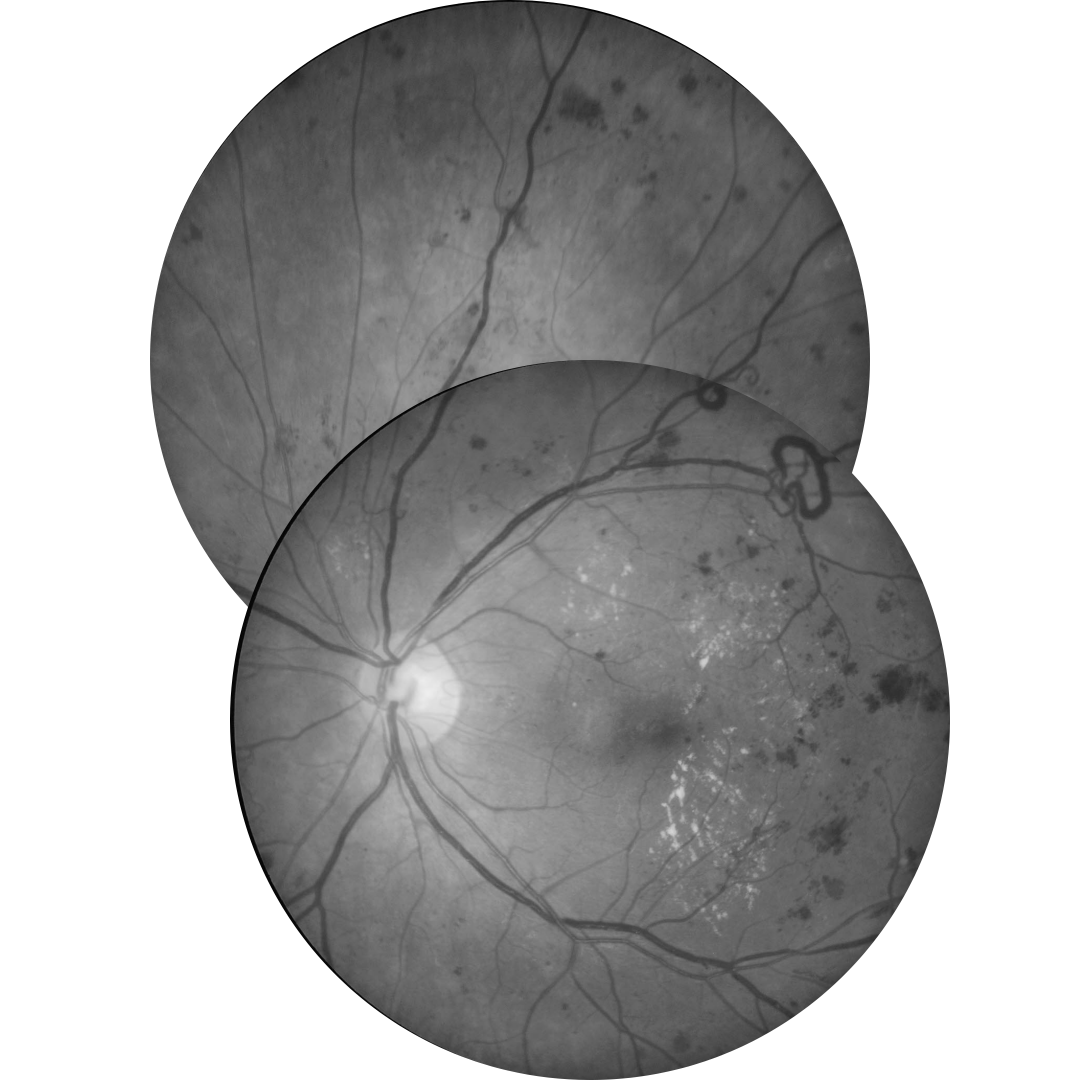

In diabetic retinopathy, macular oedema results from increased vascular permeability and a breakdown of the blood retinal barrier. These pathological processes cause leakage of lipids, proteins and serous fluid into the retina or subretinal space.

Clinical signs of macular include hard exudates and/or intraretinal oedema.

Hard exudates are discrete, yellow-white lipid deposits that may be isolated, diffuse, circinate (circular), or star-shaped. With OCT, they appear as intraretinal hyper-reflective deposits, usually in the outer plexiform layer (OPL) or outer nuclear layer (ONL). The presence of hard exudates may indicate either past or present macular oedema.

Intraretinal oedema may be appreciated clinically as retinal thickening, however can be missed in the early stages. OCT imaging may show either diffuse thickening or discrete intraretinal cystic spaces. Macular oedema may present in the absence of hard exudates, making it difficult to detect during a clinical examination or on fundus photography. For this reason, macular OCT scans are highly recommended for patients with a medical history of diabetes, particularly when other signs of diabetic retinopathy are present, macular oedema is suspected, or visual acuity is reduced.